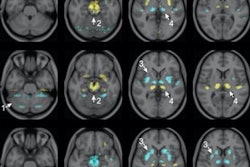

Visual comparison of reduced scan time PET images before and after denoising by MCDNet-2, with those of the normal scanning time of 20 minutes.The denoised results of the one-minute and two-minute PET images were overly smooth and blurry, the researchers reported. The denoised results of the five-minute and 10-minute PET images, however, showed a high similarity with the ground truth 20-minute PET images.